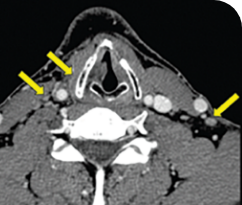

THYROID CANCER PATIENTS WITH METASTATIC DISEASE

BASELINE

AFTER 2 MONTHS OF TREATMENT

56-YEAR-OLD FEMALE WITH MULTIPLE METASTASES3

PATIENT CASE:

METASTATIC, RAIa-REFRACTORY,

PAPILLARY THYROID CANCER1

- 56-year-old female with PTCa that had metastasized to multiple sites, including the brain

- Progression after first- and second-line systemic treatment

- PRa after 4 weeks on VITRAKVI® (larotrectinib); CRa after 8 weeks

- At last assessment, complete response was sustained over an 11-month period

Clinical presentation1

- Patient was assessed to have metastatic, rapidly progressive, RAl-refractory PTC based on imaging that revealed multiple metastatic sites, including the neck, mediastinum, lung, scalp, and bones

- Biopsy of a scalp lesion helped to confirm the PTC metastasis

- Metastases to the brain and liver were observed after progression on systemic treatments

Prior treatments and outcomes1

- Prior treatments included surgery, RAI, a combination of zoledronic acid and sorafenib, external beam radiotherapy, and then lenvatinib

Testing1

- With no further treatment options, the decision was made to perform genomic testing. NGSa testing was performed on a scalp biopsy and revealed an ETV6a-NTRK3a gene fusion. The scalp biopsy had been performed 1 year earlier.

VITRAKVI treatment1

- VITRAKVI 100 mg twice daily orally

Response to VITRAKVI1

- After 8 weeks on VITRAKVI, all target lesions had disappeared, demonstrating a complete response

- The complete response was sustained over 11 months of treatment with VITRAKVI

- Patient experienced Grade 1 fatigue and mild hepatic enzyme elevation

Response in primary and metastatic lesions1

MRIa imagery of the lungs. Arrow indicates large target lesion in left lung.1

SCAN 1: LUNG

MRIa imagery of the brain. Arrow indicates large target lesion in left lung.1

aMRI, magnetic resonance imaging.

Images courtesy of Dr Fabian Pitoia.